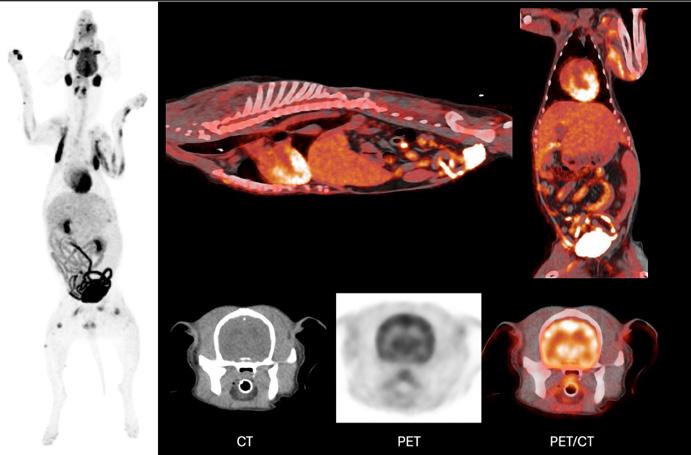

UWVC now offers PET-CT, redefining how diseases are diagnosed and treated. The technology, which has been used for years in human medicine, represents a major leap in diagnostics at UWVC, especially in oncology. The non-invasive, whole-body scan can detect disease earlier than traditional imaging and can help distinguish between benign and malignant masses. PET-CT also supports sports medicine for canine and equine patients by identifying injuries and monitoring recovery.

“PET-CT offers a unique opportunity for translational research, where breakthroughs in veterinary care can directly benefit both animals and people,” says Samantha Loeber (Department of Surgical Sciences), clinical associate professor of diagnostic imaging.